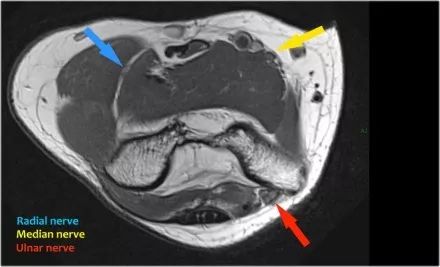

尺神经:在这里,我们看到了肘管内的尺神经。尺骨侧支带的后带形成隧道的底部,而支持带形成屋顶。

该患者有尺神经神经病变。肘管综合征是一种常见的周围神经病变。它产生于肘管内尺神经,其中该神经传递肘管支持带的下方的压缩。

肘管综合征的可能原因● 过度使用● 由于纤维组织中的先天性松弛,尺神经半脱位● 肱骨骨折伴游离体或愈伤组织形成● 由上髁或鹰嘴引起的关节炎● 存在肌肉异常● 软组织肿块:神经节,脂肪瘤,骨软骨瘤,继发于类风湿性关节炎的滑膜炎,感染(例如结核病)和出血。

当他们将尺神经带出隧道时,他们把它放在哪里,它可以是皮下,肌肉下或肌肉内。

因此,当我们回到图像时,您会发现很难找到神经。任何这些皮下结构都可以是转位神经。一种方法是远端跟随结构,直到你发现远端的尺神经位于由脂肪包围的前臂近端的正常位置。然后当你向近端跟随它时,你会发现这是皮下移位。

在这种情况下,有神经炎。神经增大。在T2W图像上有高信号。另一个标志是在矢状图像(箭头)上看到的束的不均匀扩大。

桡神经:在桡骨头水平可以最好地识别桡神经,在那里你可以看到桡骨隧道中的浅表和深支(箭头)。这是寻找桡神经的非常一致的地方。

深分支形成后骨间神经,穿过Frohse拱门(箭头)的旋后肌。